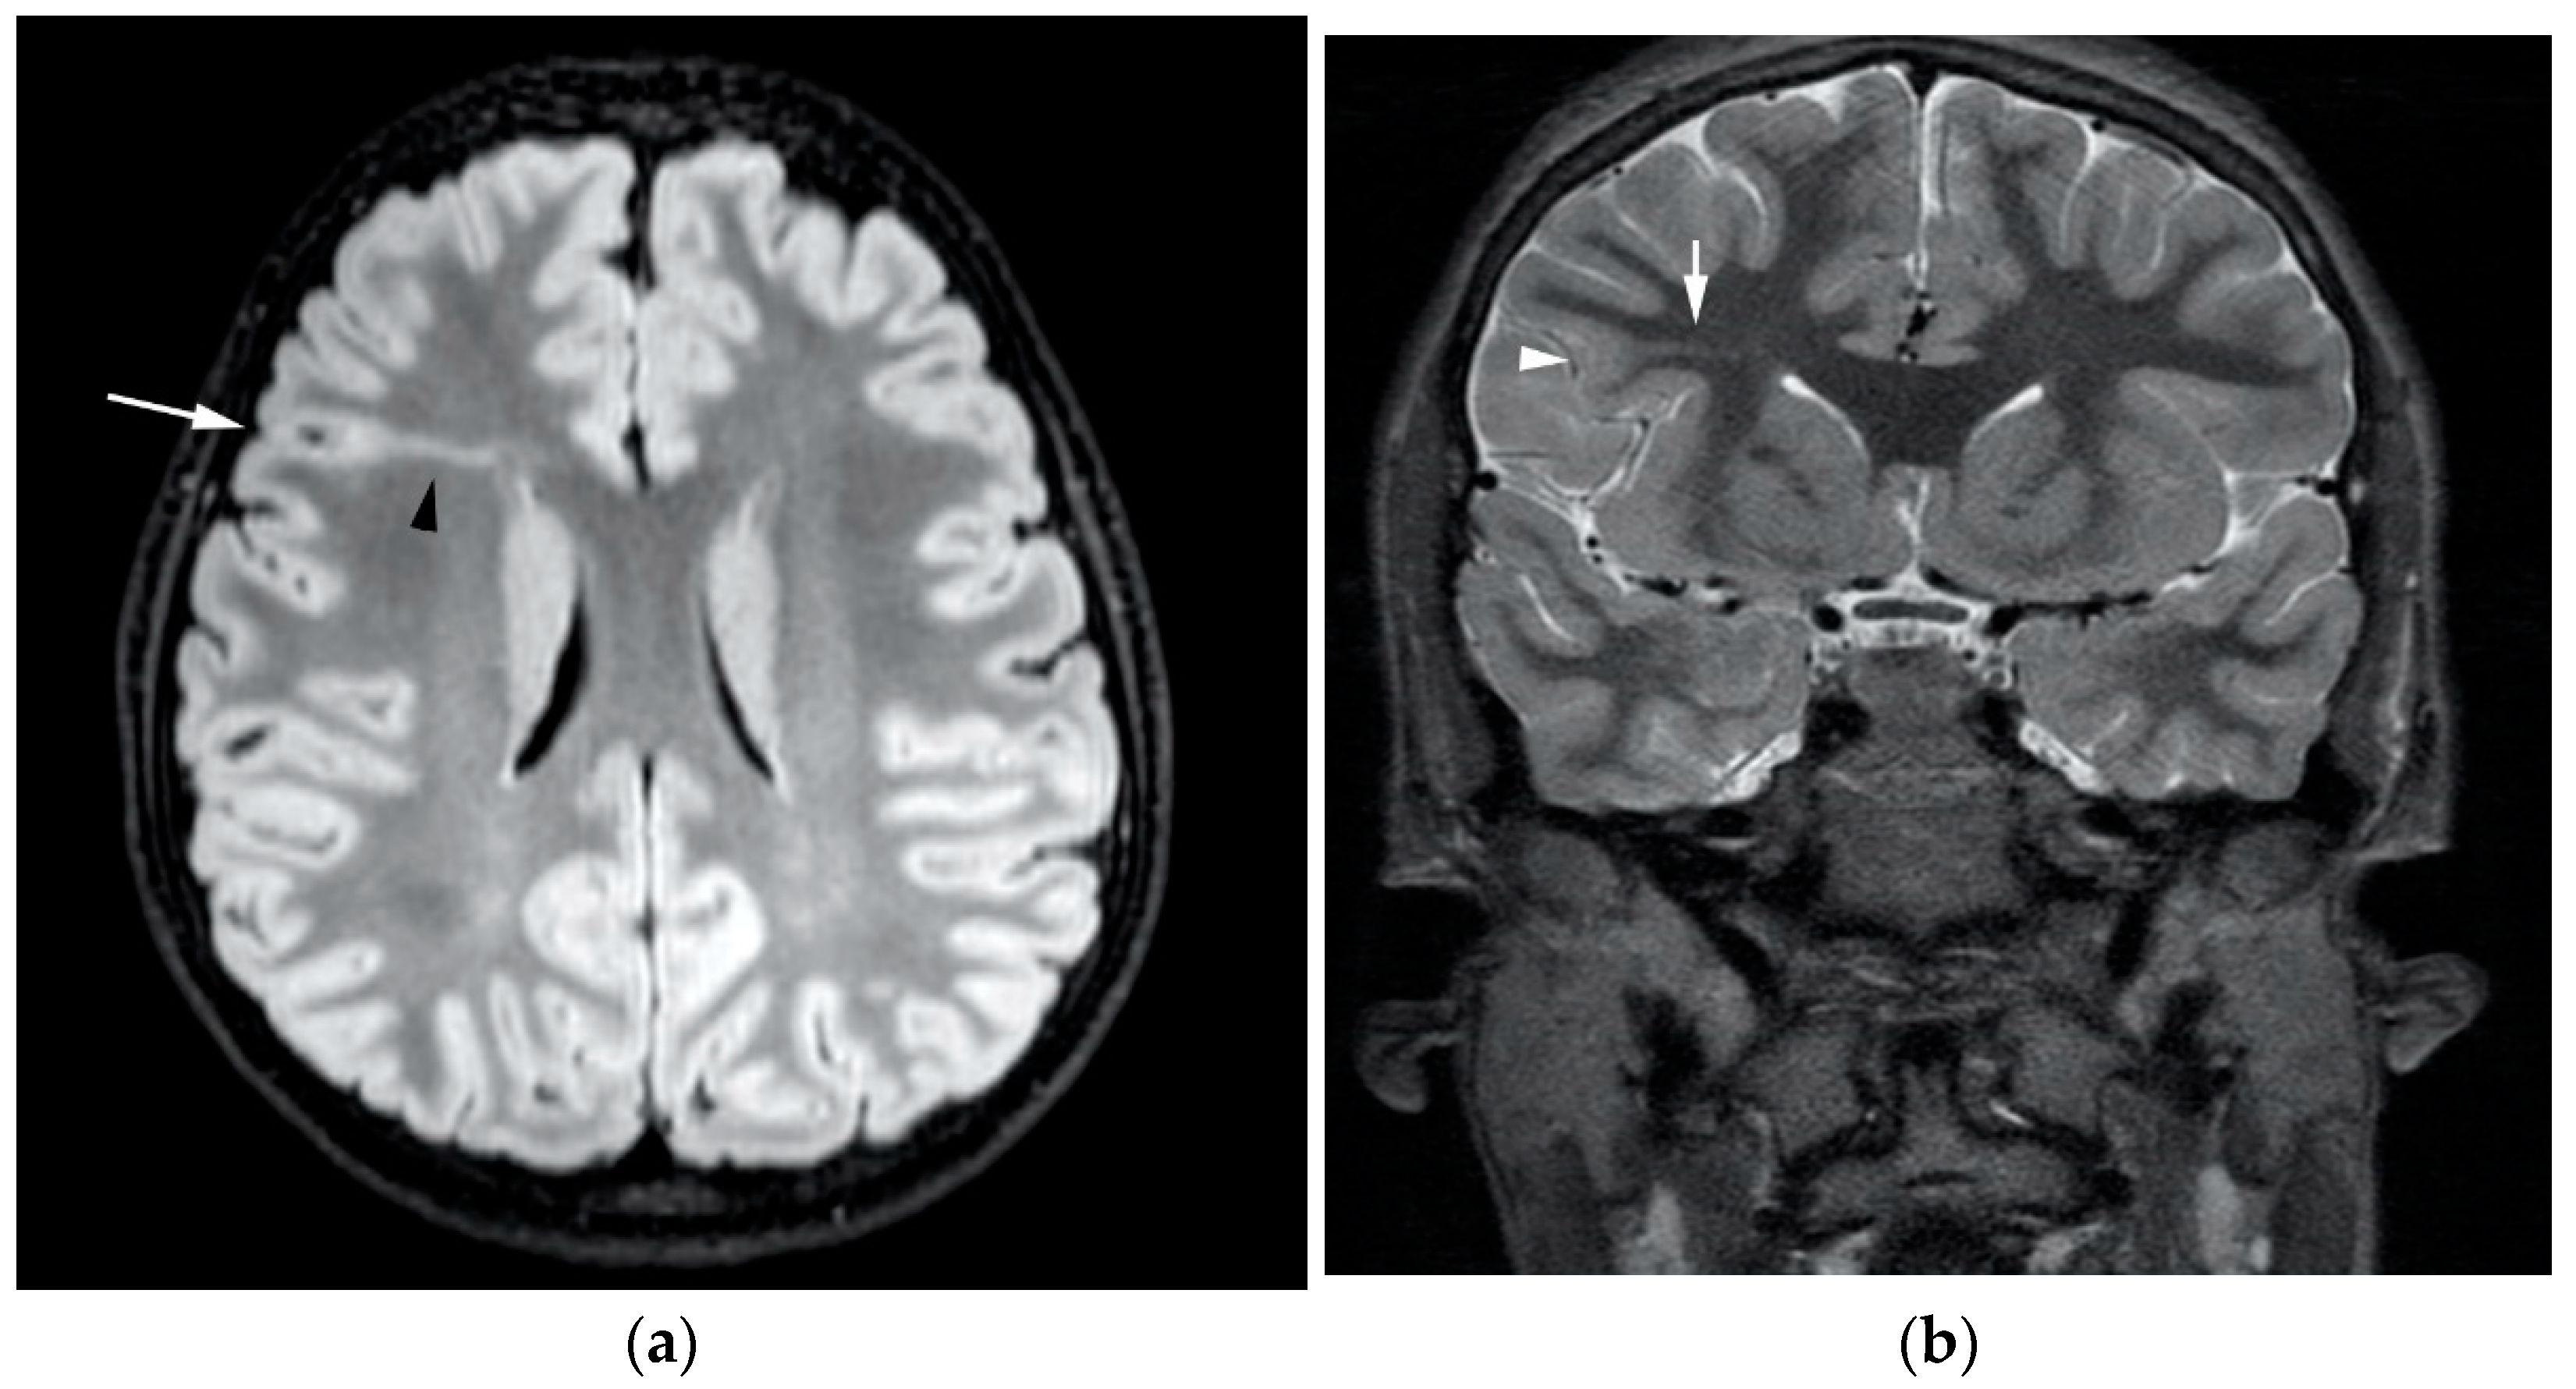

3.1. Heterotopia